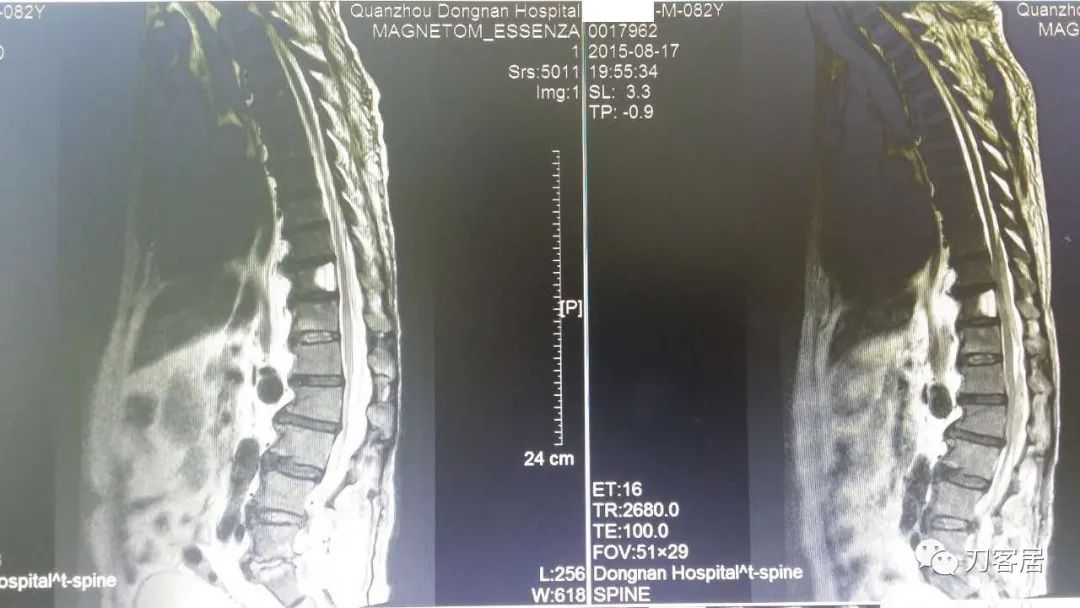

加注图4. 2015年8月17日术后5天,复查腰椎MRI提示术后改变,此平面图并没有见椎管内异常改变。

加注图5. 2015年8月17日术后5天,复查腰椎MRI提示术后改变,此平面图现在看,似乎在腰1-3椎管后方有异常信号改变,但当时手机上看,咨询我的时候,我并没有看出来,这是在电脑上操作,放大图看,似乎这里还是有问题的,但腰4-5,腰5骶1平面,椎管内信号紊乱,应该是手术后的正常表现。

加注图6-加注图7. 腰4-5、腰5骶1平面,可见手术入路形成的减压窗口。椎管内无血肿压迫。

加注图10: 腰1-2椎管内后方可见梭形占位信号改变。

加注图11. 腰1-2椎管内后方可见梭形占位信号改变。

加注图12. 术前腰椎MRI,提示腰4-5,腰5骶1椎间盘突出,腰1-2椎管内无占位病变的信号。

加注图13. 术前腰椎MRI,提示腰4-5,腰5骶1椎间盘突出,腰1-2椎管内无占位病变的信号。